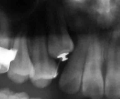

治療中